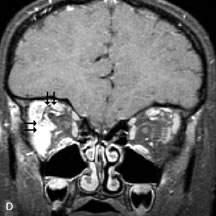

Contrast agents composed of paramagnetic or superparamagnetic materials can alter tissue properties to improve the MRI detection and characterization of certain pathologic lesions. Gadolinium diethylenetriaminepentaacetic acid (Gd-DTPA), the only paramagnetic agent currently approved in the United States for clinical applications, shortens the relaxation times of adjacent protons (hydrogen nuclei) and results in a bright signal on T1-weighted images. Gadolinium, like most heavy metals, is toxic in its nonchelated form but is safe when strongly bound to DTPA, which serves to eliminate its biologic toxicity. It is administered intravenously and is generally considered safer than iodinated radiographic contrast materials used for CT scans and arteriograms. It has little immunologic, systemic, and renal toxicity.20 Gd-DTPA has been shown to effectively detect disruption of the blood–brain barrier and delineate orbital tumors, such as meningiomas, gliomas, hemangiomas, and metastases (see Lacrimal Gland Tumors and Inflammatory and Lymphoproliferative Lesions in the section on Orbital Diseases). It also appears promising in identifying areas of altered circulation due to inflammation, ischemia, soft tissue injury, and neoplasia.7,8,21,22

MR images are produced by signals arising primarily from protons attached to either lipids or water. The protons from water and lipid resonate at slightly different frequencies. Spatial encoding of the x and y coordinates of the MR image from a given pulse sequence requires both phase and frequency information to properly map the signal information to its respective pixel. A well-known phenomenon, chemical shift artifact, is produced when water and fat protons lie in close proximity to each other. Because of the slight difference in the resonate frequencies of the adjacent fat and water protons, they are spatially mismapped in the frequency-encoded direction of the MR image, producing a dark artifactual band on one side of the interface and a bright band on the other side. This results in loss of anatomic detail in MR images of body parts, such as the orbit, that contain both lipid and water. Numerous techniques have been devised to suppress fat signals and improve visualization of lesions that develop in areas of high fat content, such as the orbit (see Intraocular Tumors, below). Three basic methods are in current use: T1-adependent suppression (e.g., short inversion time inversion recovery [STIR]), frequency-selective methods (e.g.,chemical shift selective imaging [CHESS]), and phase-dependent methods (e.g., Dixon, Chopper methods).8,22–24